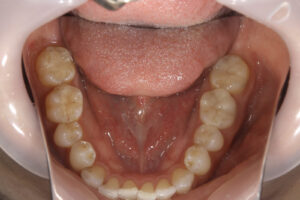

Ceramic inlay

ceramic onlay

Ceramic inlay, ceramic onlay, ceramic

Ceramic inlay, ceramic onlay,

- セラミックインレー・アンレー

内: セラミックインレー1本/80,000円、 セラミックアンレー80,000円 - 治療期間

- 他の歯科医院にて部分的な治療を受けたが、転居をきっかけに、見た目が良くない・噛めないとのことで再治療を希望された。他の医院に行こうとしたところ知り合いに当医院を勧められ来院した。アングルクラスⅠであった。

- 全顎的に着色が見られ、天然歯の変色が見られた。アングルクラスⅠで上下顎前歯部に叢生が見られ、クリーニングの後、上下顎臼歯部にセラミックインレー・アンレーを装着した。

- 審美的な仕上がりで、患者自身も満足した。半年経過し良好である。

現在は2〜3ヶ月おきのメインテナンス中である。

セラミックインレー・アンレーには欠け易いといったリスクがあるためナイトガードは必須である。

特に清掃が重要である。